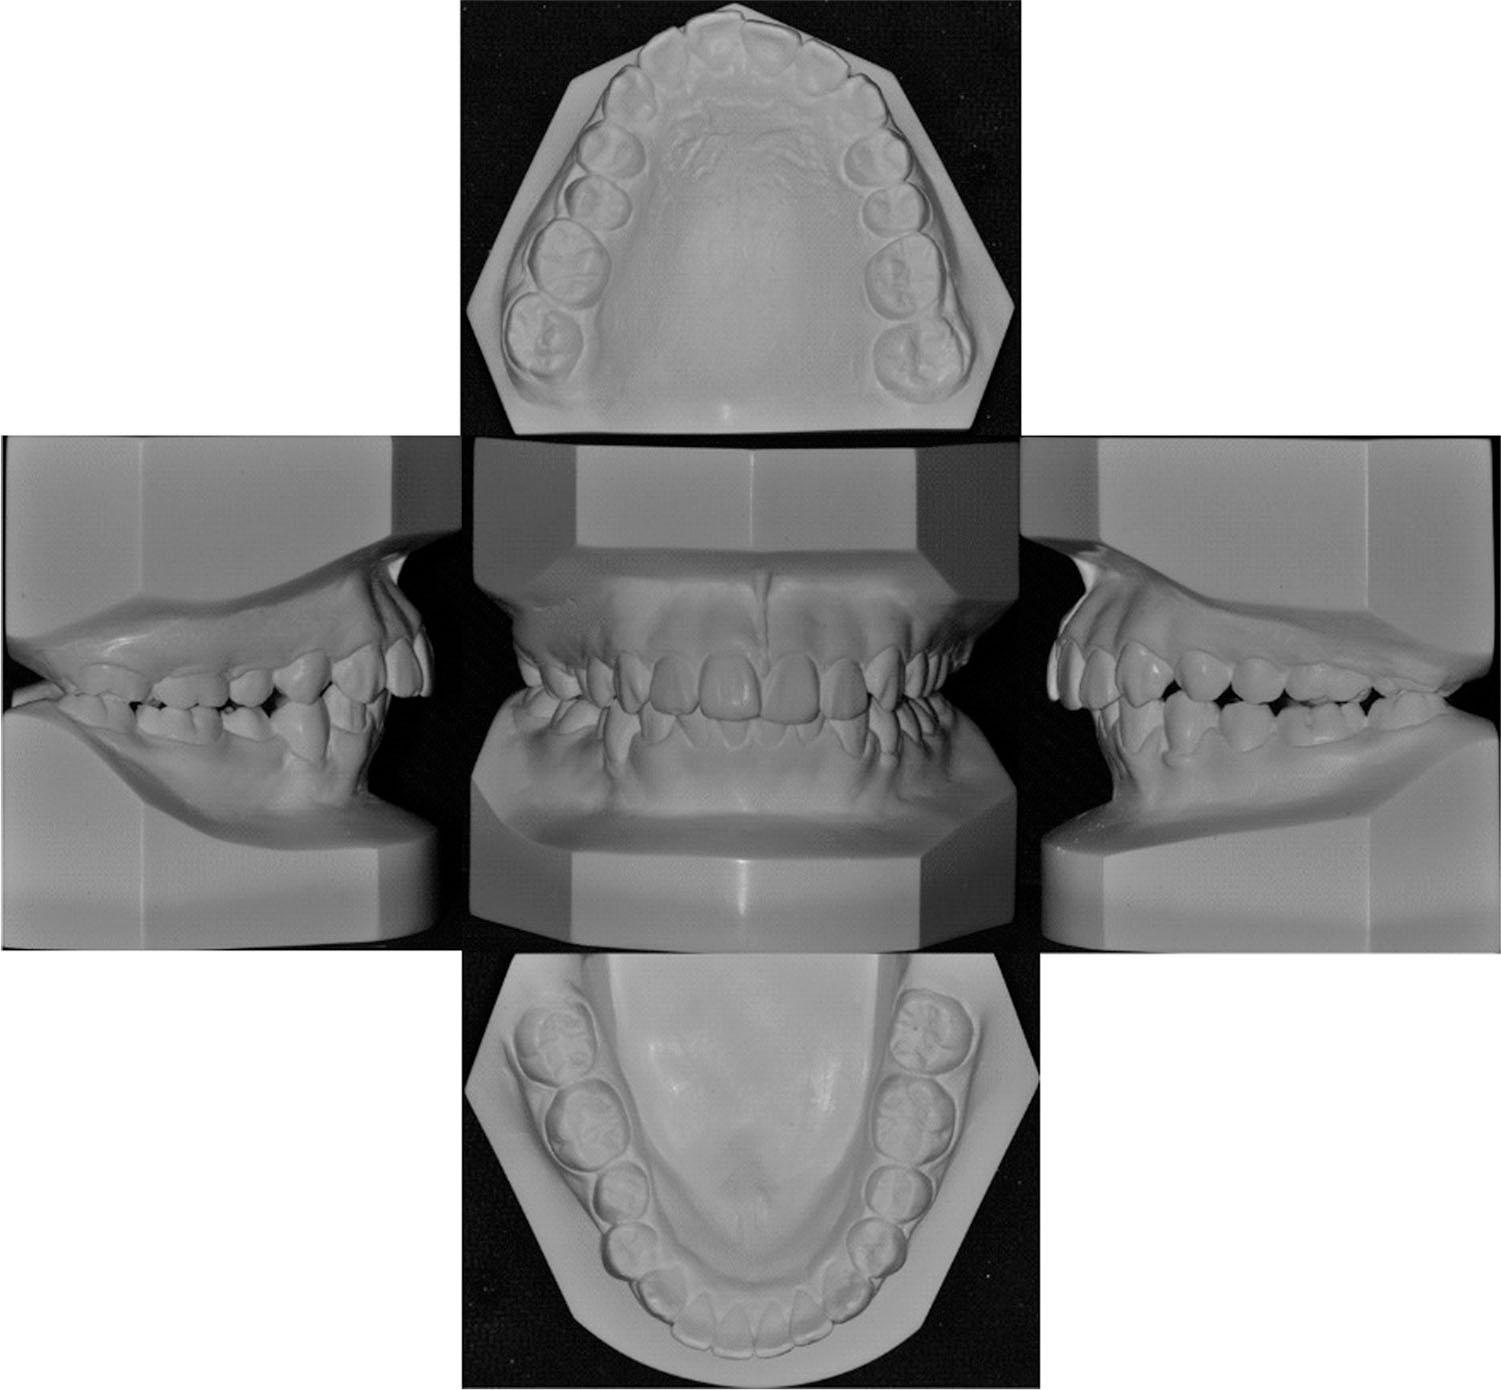

Figure 7.

Figure 8.